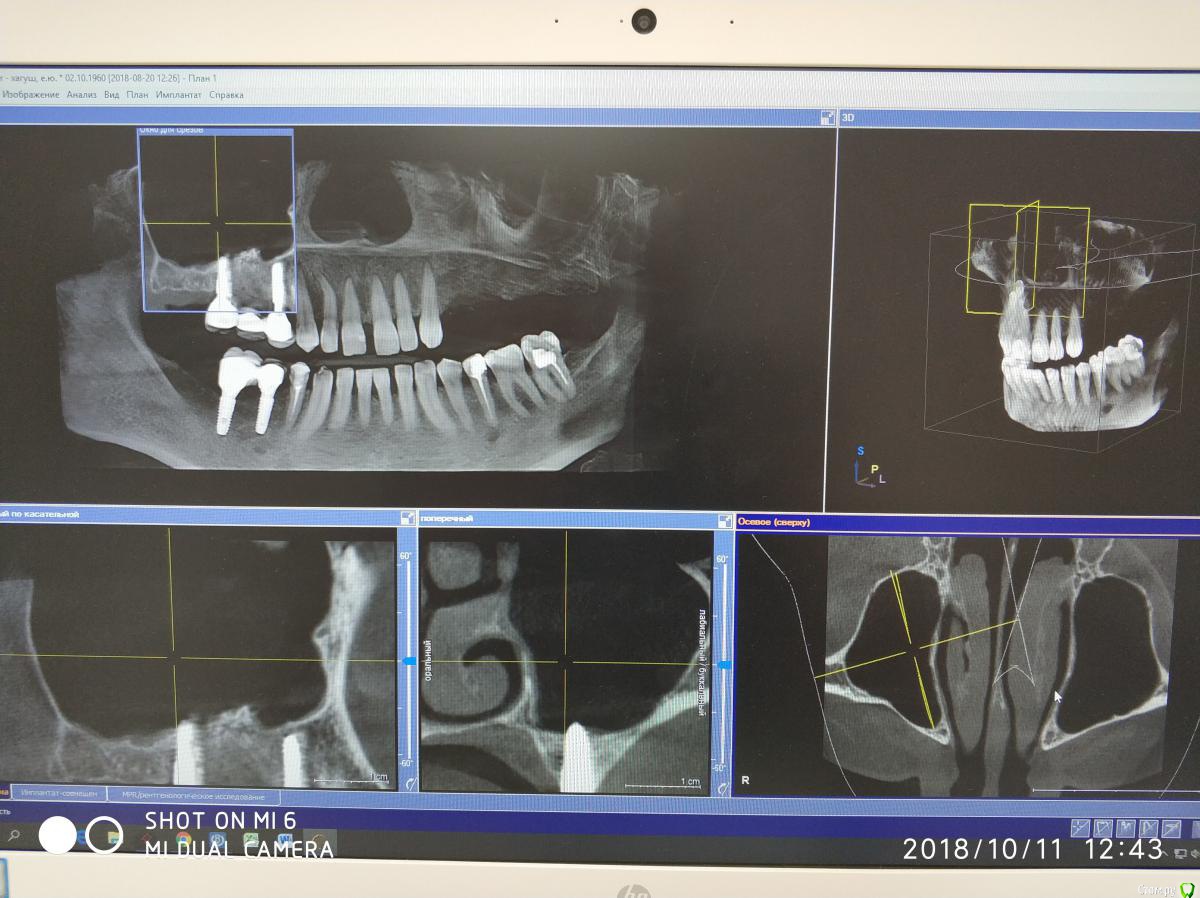

Nazim_NV86 Опубликовано 11 октября, 2018 Автор Поделиться Опубликовано 11 октября, 2018 Появилась свежая КЛКТ Ссылка на комментарий

Nazim_NV86 Опубликовано 11 октября, 2018 Автор Поделиться Опубликовано 11 октября, 2018 (изменено) Женщина. Примерно 50-53. Скрины синуса сделал, но замотался и забыл выложить. Синусы вч оба чистые. Слева правда есть маленькое мукоцеле. Сегодня предложил ей снять коронки и походить с формирователями. По семейным причинам уехала к дочери помогать. Отложили на месяц. Так у нас есть месяц на расследование ) Изменено 11 октября, 2018 пользователем Nazim_NV86 Ссылка на комментарий

Nazim_NV86 Опубликовано 12 октября, 2018 Автор Поделиться Опубликовано 12 октября, 2018 Срезы пазух. На чувствительность языка жалоб не слышал. Как приедет тесты сделаю. Ссылка на комментарий

Nazim_NV86 Опубликовано 2 февраля, 2019 Автор Поделиться Опубликовано 2 февраля, 2019 (изменено) В продолжении беседы:02.08.16г. была микрогайморотомия справа ( ДЗ выписке: киста г.п.).10.08.17г. поставлены 14,16 с открытым синус-лифтингом(апатос микс+эволюшн). Синус был чистый как до, так и после операции. Соустье работало.18.01.18г. поставлены 45,46. После операций никаких особенностей. 19.04.18г. 4 фдм. И примерно в это время (со слов) появились проблемы с запахами. Коронки сданы 29.05.18г.При допросе (настойчивом) оказалось что пациентка часто болеет ОРЗ и постоянно лечится. Аллергоанамнез оказался впечатляющий. В анкете об этом нет информации. Перечень всего на что у неё была аллергия большой. Попросил перечислить мне на бумаге.На контр осмотр не пришла, поскольку снова заболела. Иммуноглобулины: А - 0,39 (0,65-4,21); М - 0,72 (0,33-2,93); G - 18,64 (5,52-16,31). от 23.01.19г Попросил сдать сам.Заключение МРТ от 21.08.18г. МР-картина очагов глиоза в белом веществе головного мозга сосудистого характера, умеренной наружной заместительной гидроцефалии. Данных за объёмные патологические образования и ишемические изменения не получено. Жду результатов других анализов (направлял терапевт). Изменено 2 февраля, 2019 пользователем Nazim_NV86 1 Ссылка на комментарий